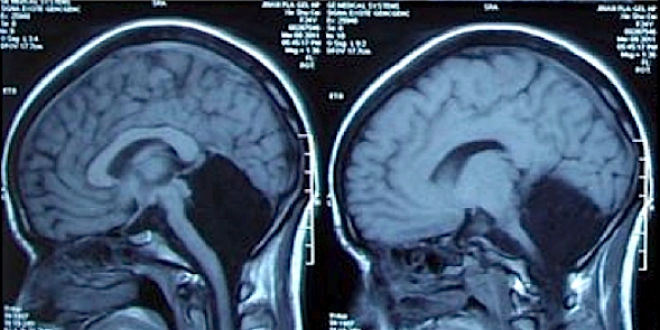

Depuis plus d'un mois, la jeune femme souffrait de nausées et de vomissements. Admise dans un hôpital de la province de Shandong (Est de la Chine), la patiente a bénéficié d'un scanner cérébral. Celui-ci a révélé, en termes médicaux, une "agénésie cérébelleuse primaire complète". C'est-à-dire qu'aucune structure reconnaissable n'était présente au niveau de la zone normalement dévolue au cervelet.

Le cervelet est une structure du cerveau de petite taille, située sur sa face postérieure. Sa principale fonction est d'intégrer les signaux moteurs reçus de tout l'organisme (sensations musculaires, ordres issus du cortex…) afin de permettre la coordination et la synchronisation des gestes et des mouvements.

Le cervelet est indispensable pour l'apprentissage de la motricité fine (mouvements précis et ajustés aux sensations, notamment en lien avec l'équilibre). Il contribue, dans une moindre mesure, à la régulation de l'attention et du langage."La plupart des personnes ayant une agénésie cérébelleuse primaire complète sont les nourrissons ou les enfants présentant une insuffisance mentale grave, une épilepsie, hydrocéphalie et d'autres lésions macroscopiques du système nerveux central", détaillent les médecins chinois, qui ont décrit ce cas fin août 2014 dans la prestigieuse revue Brain.